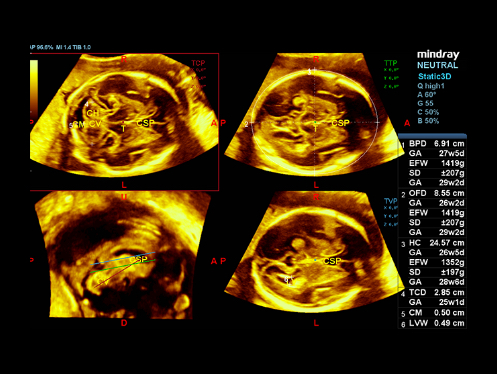

El ecГіgrafo DC-80A con X-Insight proporciona una soluciГіn excepcionalmente inteligente para la completa salud de la mujer, desde fertilidad hasta el cribado prenatal y asistencia sanitaria posparto.

ImГЎgenes ClГӯnicas